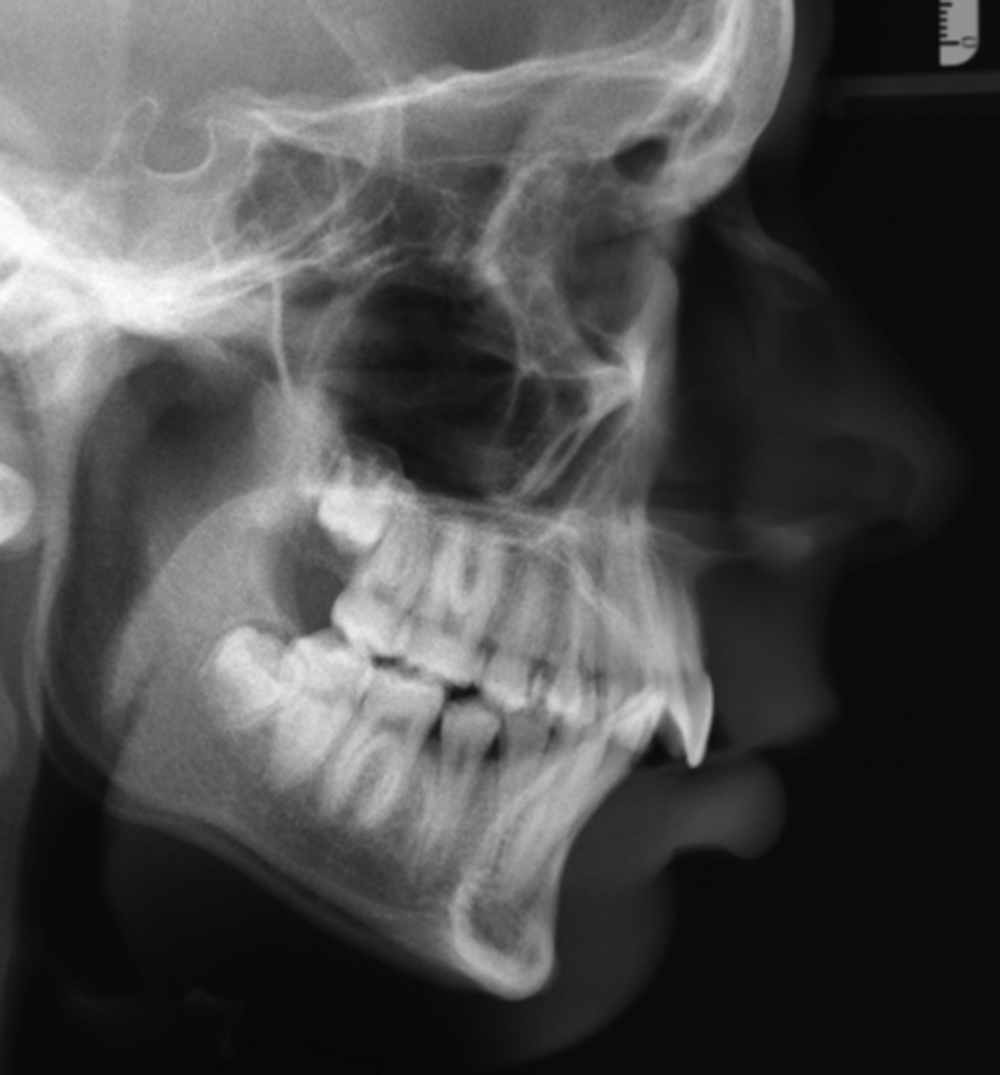

Routine radiological examination is a necessary part of the orthognathic workup. In past times the standard was to perform a lateral cephalogram, as well as plain AP films. This was later supplemented with the panograph, and finally supplanted by the cone beam computed tomography (CT) scan. More so in the present day than previously, three-dimensional imaging has become the standard in many centers with the advent of cone beam CT scans. These cone beam scans subject the patient to a much lower dose of radiation than traditional CT imaging while maintaining adequate image quality. The three-dimensional scans also allow for virtual surgical planning to be performed, thus planning surgical movements expediently as compared to what was previously a time-consuming, multistep process of model surgery that was fraught with small errors that could further be amplified with each step of the process ( Figs. 21.8 and 21.9 ). Virtual surgical planning has greatly streamlined the workflow process, eliminating the tedious steps involved with model surgery and allowing for preoperative visualization of each step in the surgical process. Osteotomies with subsequent bony movements can be planned and visualized in all dimensions, making fine-tuned adjustments to the yaw (i.e., rotation on the Z axis), pitch (rotation on the X axis), and roll (rotation on the Y axis) that were previously difficult to do with traditional model surgery. Intermediate and final surgical splints are also fabricated during these planning sessions. Studies have also shown increased accuracy with virtual planning when compared to traditional methods ( Fig. 21.10 ).

Radiographs are also useful when determining the appropriate time to operate on a growing, peripubertal patient. Serial cephalograms can be taken 6–12 months apart and compared for growth changes, as well as cervical spine radiographs ( Fig. 21.11 ). AP hand and wrist films can be used to demonstrate whether the epiphyseal plate has closed, thus predicting cessation of maxillomandibular growth.

A baseline understanding of cephalometric analysis is also prudent for the operating surgeon. Various studies and analyses exist to examine the relationships of the maxilla, mandible, and skull base when viewing these structures on a lateral cephalogram. Looking at overall facial proportions, the upper facial height can be approximated measuring the distance from nasion to A point, whereas for lower facial height it is from A point from menton. The ideal facial plane is viewed by creating a vertical line, perpendicular to the Frankfort horizontal (orbitale to porion), from nasion to soft tissue pogonion. The anterior cranial base is identified as a line drawn between sella and nasion. The mandibular plane is a line drawn between gonion and menton, whereas the occlusal plane is created with a line between the maxillary and mandibular central incisors and first molars.

Other important cephalometric measurements can be evaluated when comparing the maxilla to the cranial base. This is best viewed with an angle created between the sella, nasion, and A point (SNA). The normal SNA value is 82 degrees ±3, with values greater than 85 degrees signifying a prognathic maxilla, and less than 79 degrees showing a retrognathic maxilla. The mandible is related to the cranial base by the angle between the sella, nasion, and B point (SNB). The normal SNB value is 79 degrees ±3, with a value greater than 82 degrees being consistent with a prognathic mandible, and less than 76 degrees signifying a retrognathic mandible. Chin position is evaluated by looking at the angle between sella, nasion, and pogonion (SNPg). The normal value for SNPg is 80 degrees ±3, with a value greater than 83 degrees being consistent with a protruded chin, and less than 77 degrees showing a retruded chin. A relative measure of the positioning of the maxilla to the mandible is the angle between the A point, nasion, and B point (ANB). The normal ANB value is 1–5 degrees, thus often coinciding with a class I skeletal profile. An ANB value greater than 5 degrees often coincides with a class II skeletal profile, and less than 1 degree with a class III profile , ( Fig. 21.12 ).